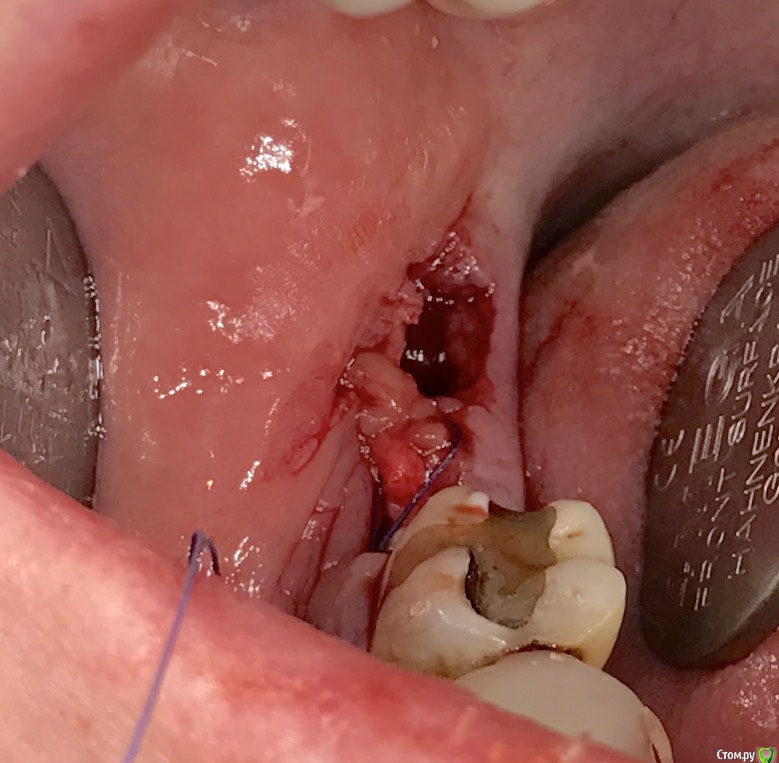

колесников Опубликовано 19 марта, 2017 Поделиться Опубликовано 19 марта, 2017 Здравствуйте коллеги! Есть несколько проблем которые мне не давали покоя своей неразрешимостью. Одна из них это постэкстракционное ведение лунки нижних восьмых. Со временем пришёл к протоколу который начал устраивать меня и пациентов. Но вылезла проблема которую никак не удавалось решить: щелевидный дефект в лоскуте у дистального корня 2го моляра. Герметизма не удавалось достичь,вторичное инфицирование со всеми вытекающими. Пробовал разные виды лоскута,швов,прф,но без особого успеха. Особенно часто такая проблема возникает при горизонтальном положении 3го моляра с редуцированной межзубной перегородкой. Наконец проблема решена. К обычному протоколу я добавил расщеплённый ротированый лоскут на питательной ножке. В результате лоскут дистально у шейки 2го моляра получается двуслойным и независимым. Если края верхнего слоя по тем или иным причинам разойдутся, у нас есть второй,по которому как по рельсам вторично наползет эпителий. Ссылка на комментарий

Doctor Vlad Опубликовано 21 марта, 2017 Поделиться Опубликовано 21 марта, 2017 Наконец проблема решена. К обычному протоколу я добавил расщеплённый ротированый лоскут на питательной ножке. В результате лоскут дистально у шейки 2го моляра получается двуслойным и независимым. Если края верхнего слоя по тем или иным причинам разойдутся, у нас есть второй,по которому как по рельсам вторично наползет эпителий. как всегда с конца читать начал, всю суть упустил... этот лоскут внутренний как пришивать? резорбируемой ниткой? и как часто получается сделать расщепленный лоскут, язычный и без того тонкий(? Ссылка на комментарий

колесников Опубликовано 21 марта, 2017 Автор Поделиться Опубликовано 21 марта, 2017 Нет сгустка-нет проблем связанных с его распадом. Конечно и графт может инфицироваться.для этого и нужен полный герметизм. Внутренний лоскут пришивается как сст. Снаружи (вестибулярно ,примерно на середине 7ки)заводится игла,подхватывается лоскут и выводится снова наружу, Натянули,зафиксировали. Расщеплять там где толсто,понятно,что не всегда это язычно. Есть ещё вариант : выделить фрагмент ретромолярно и после вести разрез по язычной кромке. Получается такая длинющая змейка,которую можно хоть в рулон свернуть. 1 Ссылка на комментарий